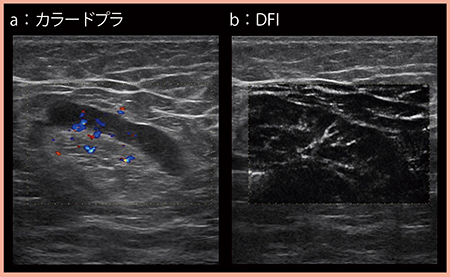

DFIは,これまで描出困難であった低流速の血流を表示する技術で,従来はアーチファクトを除去することで消えてしまっていた微細な血流を残し,より高分解能かつ高感度に描出可能となった。

図4は,乳房内に膿瘍が見られた症例の反応性リンパ節で,カラードプラでもリンパ門側からの血流が描出されているが(a),DFIでは樹枝状の微細な血流が明瞭である(b)。

図4 DFIによる微細血流の描出(反応性リンパ節)